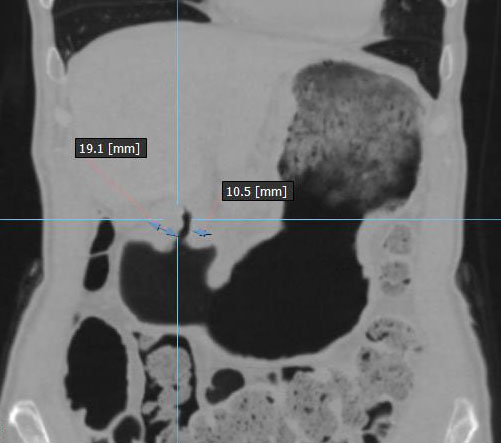

Циркулярный рак антрального отдела желудка с затруднением эвакуации химуса